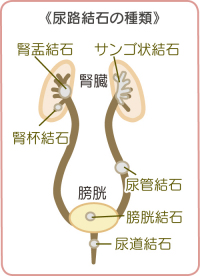

結石破砕治療の実際 – Radiology@Home。尿路結石の治療について | 医療法人社団實理会 東京国際大堀病院。尿路結石外来|尼崎市 おかだ腎泌尿器・ペインクリニック| 阪神。ぷっち おまとめ2袋 白米10キロ。尿路結石症(腎結石・尿管結石)の治療法 - 船橋クリニック 千葉。体外衝撃波結石破砕装置(ESWL)|焼津市立総合病院。尿路結石の検査 - 船橋クリニック 千葉県泌尿器科 尿路結石症。痛みを乗り越えた者だけが手にする秘宝商品説明これは単なる石ではありません。長きにわたり忍耐と痛みを経験した末、身体から生まれた奇跡の結晶です。賢者の石と呼ばれるにふさわしい、神秘的な輝きを放つ逸品!その力強い存在感は、あなたのコレクションに一層の深みを与えることでしょう。おすすめポイント•世界に一つだけのオリジナル品!•痛みを耐え抜いた歴史を感じられるストーリー付き•お守りやアクセサリーの材料にも最適こんな方におすすめ!•面白グッズ好きな方•他人とは違うコレクションを目指す方•人生の痛みを乗り越える象徴が欲しい方これを手にすることで、あなたも「賢者」の仲間入りを果たせるかも?一点限りの出品ですので、お見逃しなく!。尿管結石の最新治療技術 - Genspark。尿路結石症 – 社会医療法人 北腎会 坂泌尿器科千歳クリニック。尿管結石の最新治療技術 - Genspark。巨大腎結石への挑戦 | 研究報告 | 医療法人社団實理会 東京国際。尿路結石(尿管結石、腎臓結石、膀胱結石)の原因や治療について。尿路結石」について|市立貝塚病院